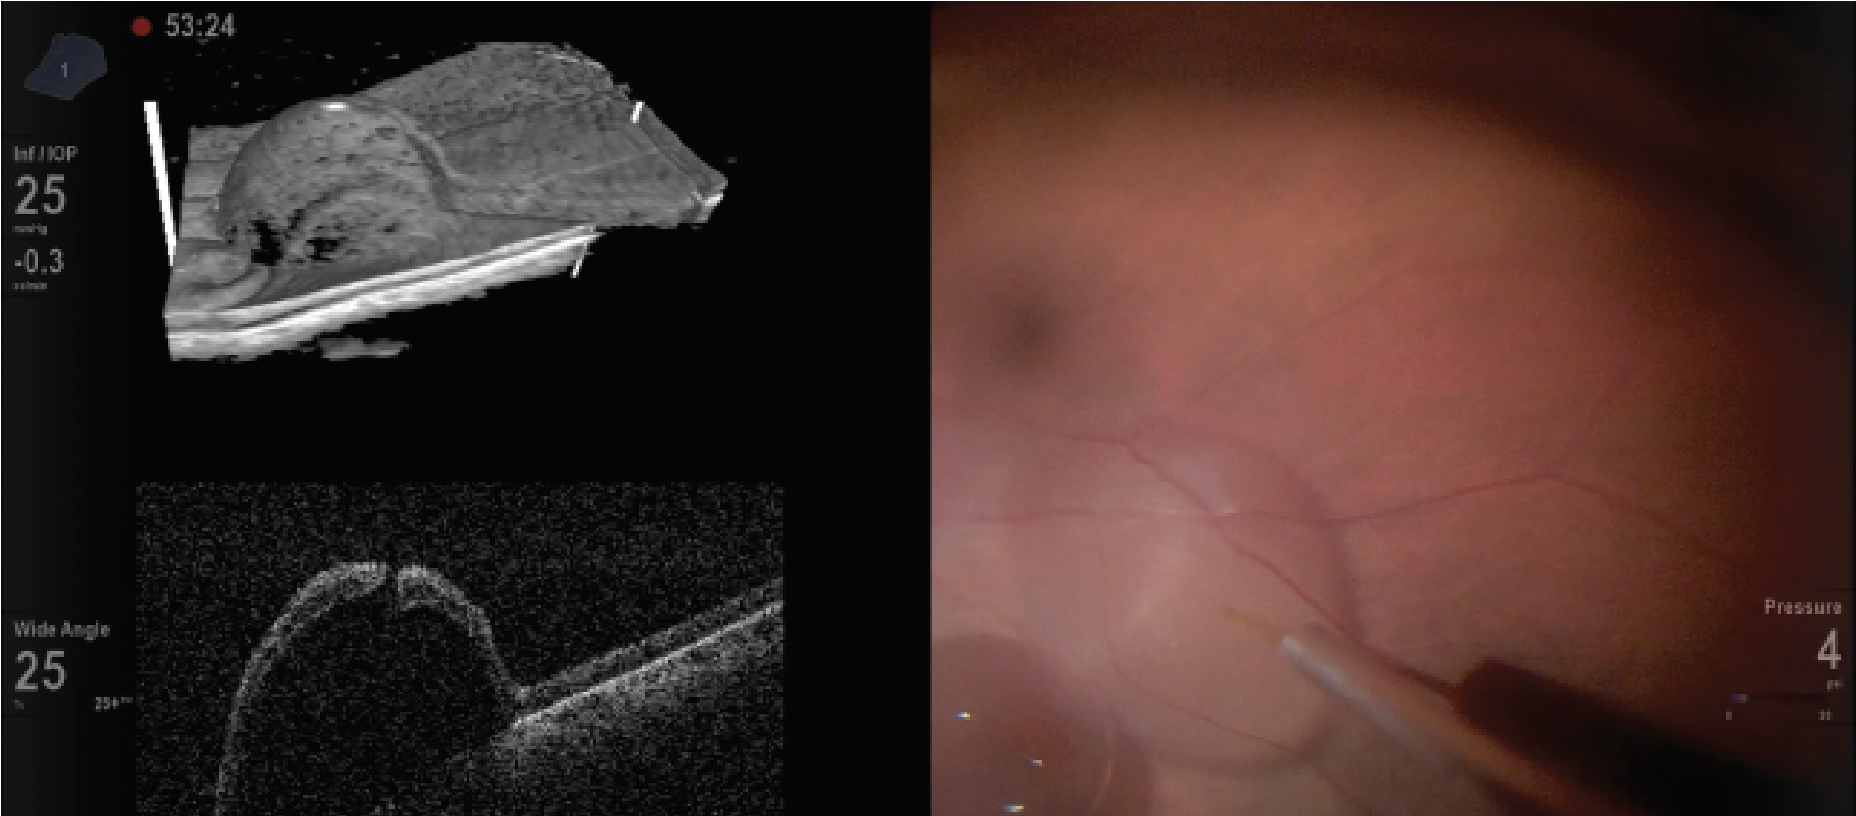

HUD can allow side-by-side or superimposed images of intraoperative optical coherence tomography images in real-time. The DISCOVER study, which evaluated microscope-integrated OCT with 3D visualization, reported its use in procedures such as macular surgery and retinal detachment repair with proliferative vitreoretinopathy.11

The surgeon can view the OCT image without looking away from the monitor. 3D HUD integrated with iOCT has also been investigated for gene therapy and subretinal tPA injection, and has aided in visualization of the retinal architecture to ensure proper delivery of subretinal drugs (Figure 3).12–17

| Figure 3. Heads-up display during gene therapy placement with intraocular optical coherence tomography. |